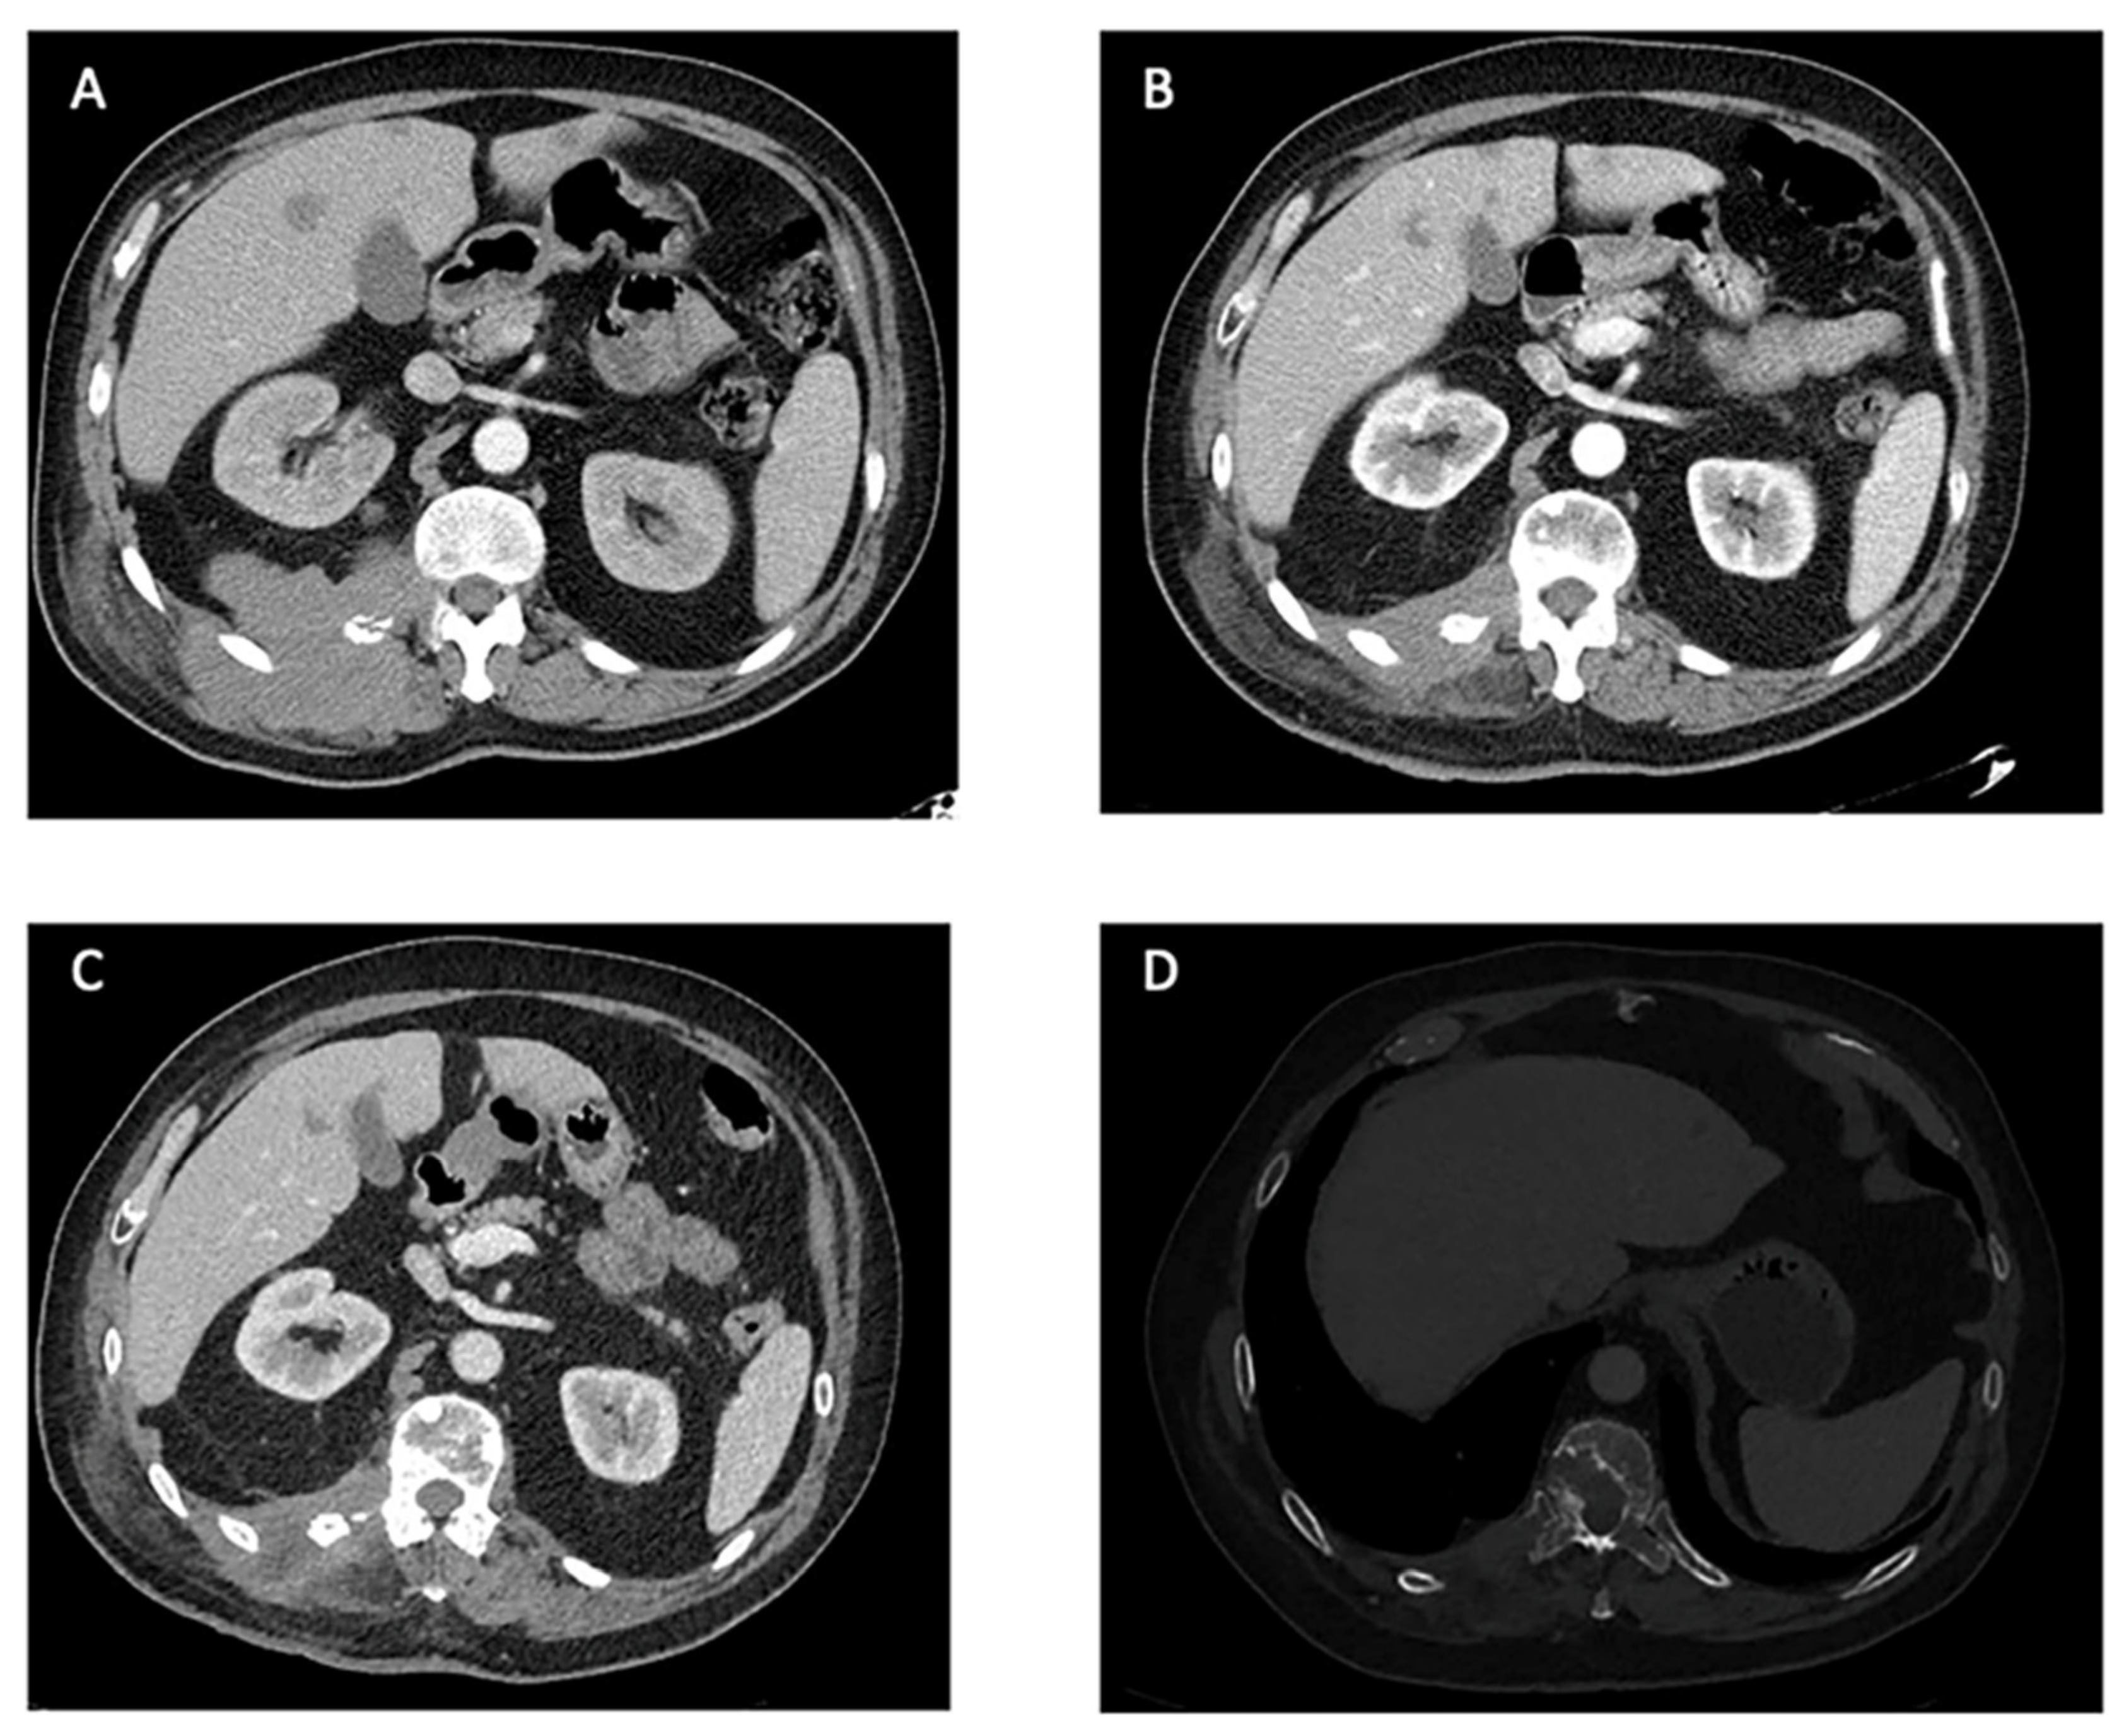

Figure 3.

Computer Tomography Scans of a patient treated with pazopanib at our center: an example of PR. (A). Locally advanced disease affecting the right paravertebral area with involvement of the right 12th vertebral transverse process and rib and metastatic liver nodes. Baseline for the treatment with pazopanib. (B). RECIST 1.1 partial response of the mass in the right paravertebral area after 20 months under treatment with pazopanib. (C). Maintained partial response on primary tumor and hepatic lesions after 25 months under pazopanib. (D). Increase in size of a bone lesion in D10 establishing mild spinal cord stenosis, 25 months after the start of pazopanib (bone window).

In our center, we treated one patient with the characteristics of these reviews, a 52-years old male with a lesion arising in the right paravertebral muscles, being superficial at diagnosis. After resection of the primary tumor, a local, lymphatic, and hepatic relapse occurred 8 years later. The initial treatment following the recurrence was chemotherapy, based on ifosfamide 1800 mg/m2 days 1–5 and etoposide 100 mg/m2 days 1–5. A total of eight courses were administered with good tolerance and stable disease as it best response. After a new progression, the patient received 25 months of pazopanib with good tolerance. Partial response was achieved according to RECIST criteria (Figure 3) and discontinuation was due to progression. The duration of treatment with pazopanib and the survival time was longer in our case than in cases reported in this review, while the results of chemotherapy were similar.

The median reported time of response duration with pazopanib was available for nine patients and was seven months. However, five patients were still on therapy at the time of the report. Eight of the patients experienced disease control with pazopanib, with four patients achieving an objective response whereas two patients experienced progression disease as the best response (Figure 3).